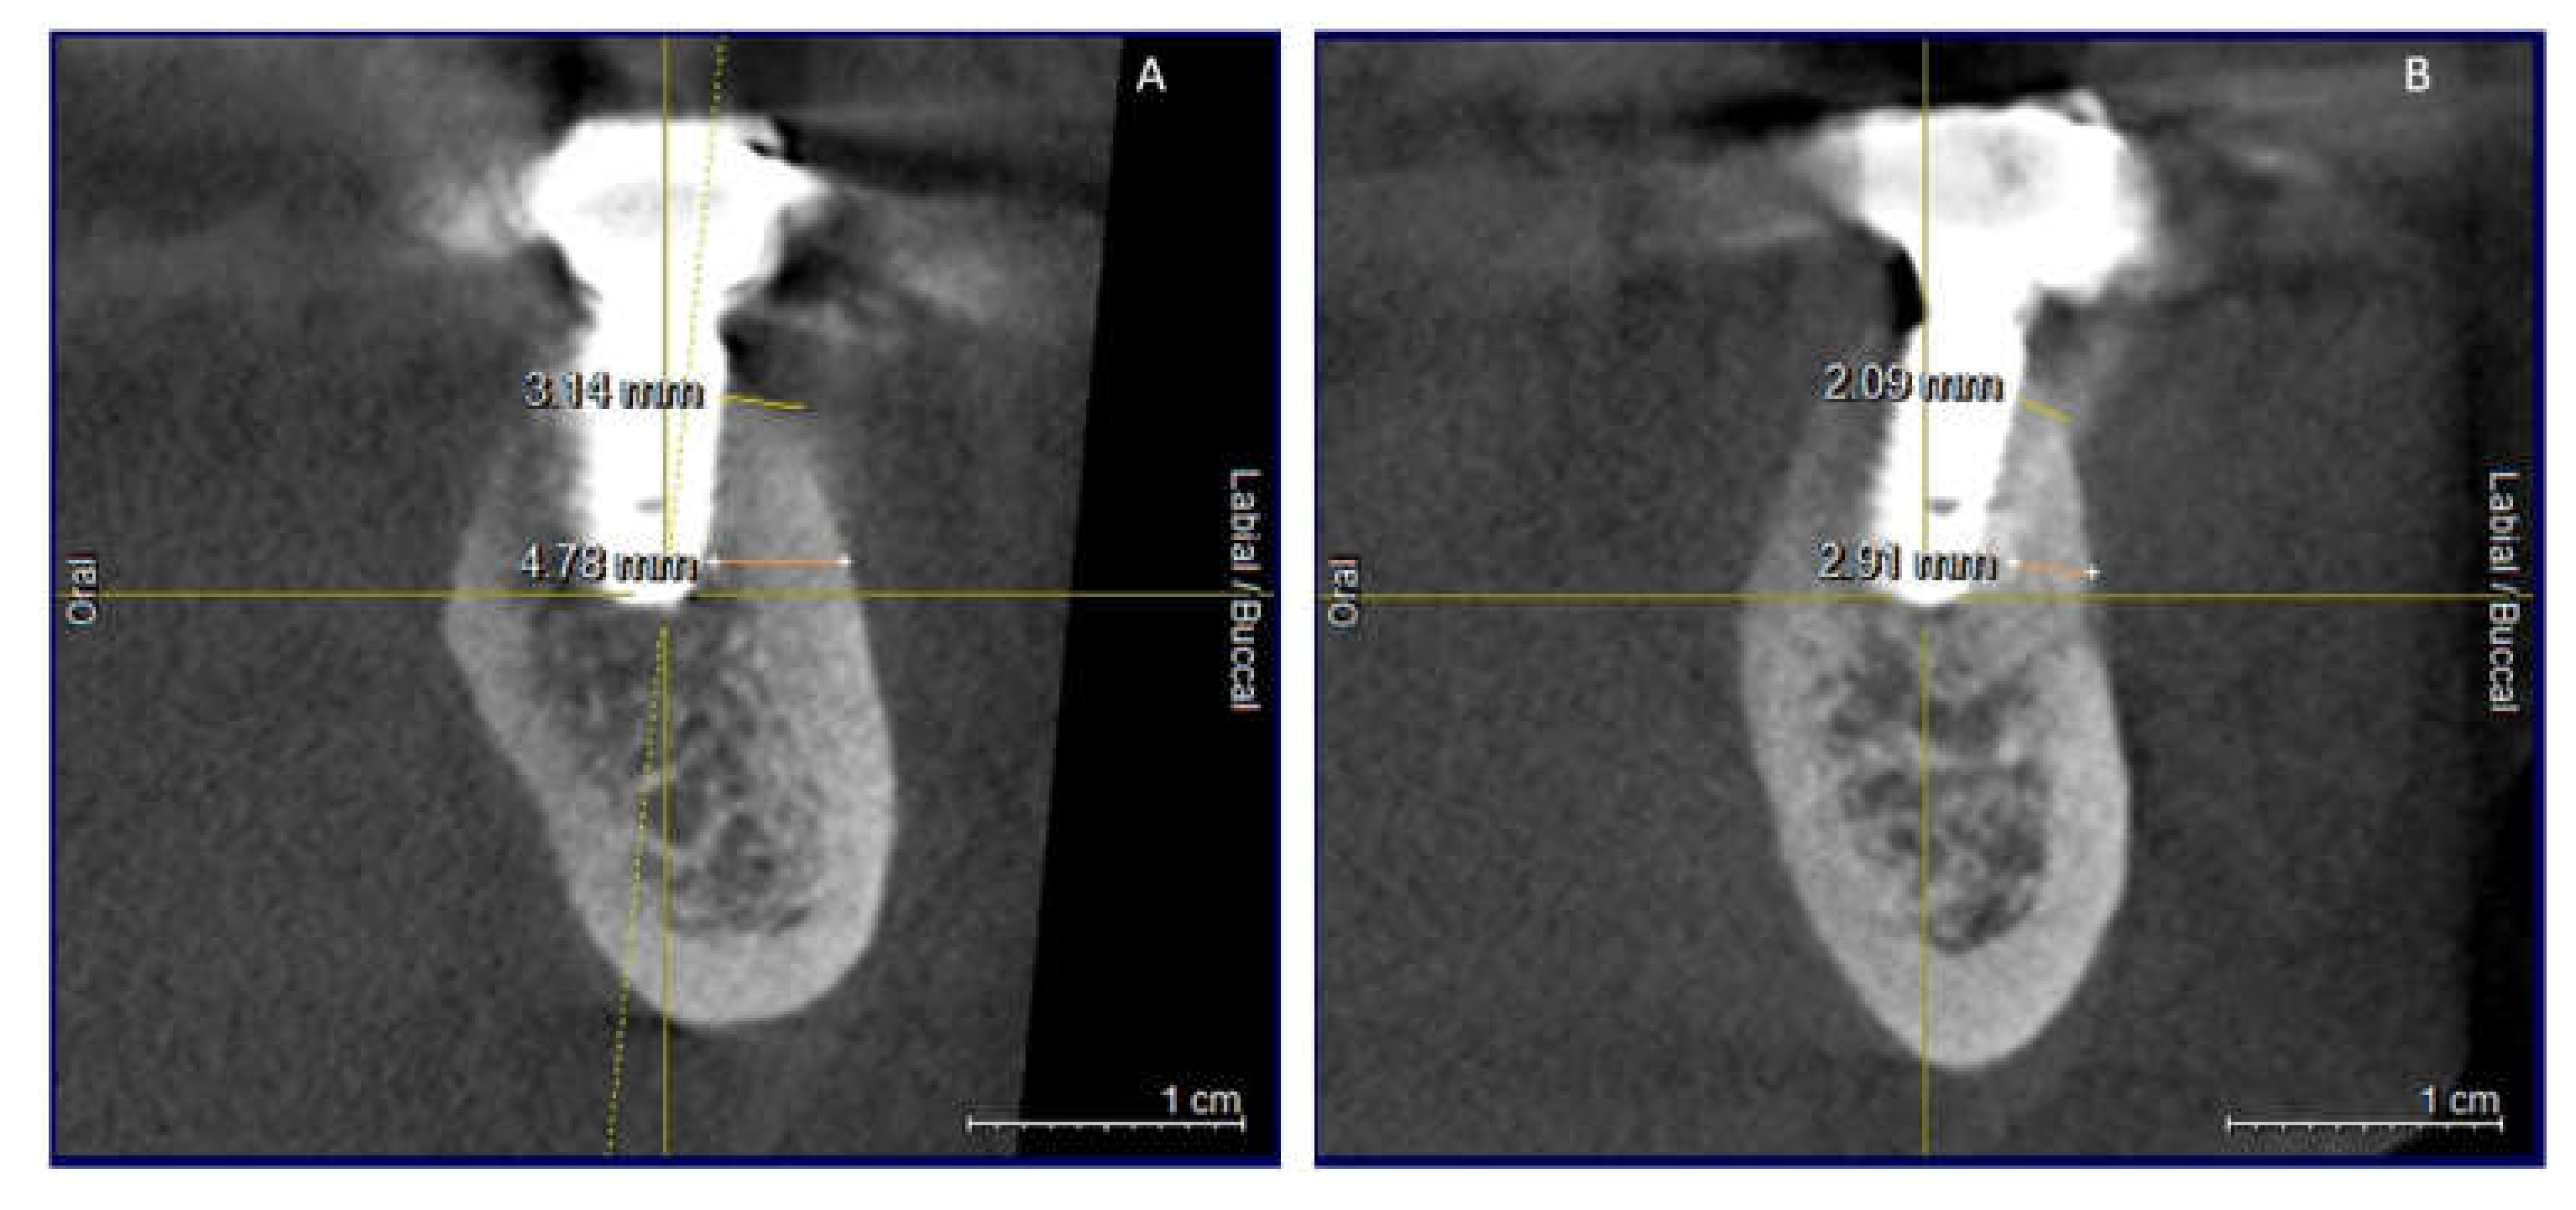

Clinical and CBCT aspects of patient from the test group, describing the stages of S-GBR technique and implant-prosthetic stage, are presented in Figure 1, Figure 2, Figure 3, Figure 4, Figure 5, Figure 6, Figure 7, Figure 8, Figure 9, Figure 10 and Figure 11. CBCT exam allows the evaluation of the horizontal alveolar bone defect and the position of the mandibular alveolar nerf (Figure 1A,B). Figure 1C,D show cross-sectional CBCT aspects of the implant sites. Figure 2 shows the narrowed mandibular alveolar bone with horizontal resorption. Figure 3 shows the exposed buccal surface of the alveolar ridge with severe horizontal resorption, after flap opening. The inserted implants (4.5 mm diameter, 11.5 mm length) and osteosynthesis screws (45° from the occlusal plan) are shown in Figure 4A. The placement of graft (autologous bone and xenograft) and collagen membrane is shown in Figure 4B. Figure 5A shows tension-free sutures, due to periosteal incisions alveolar ridge. Figure 5B shows clinical aspect at 7 months after surgery, with gingival tissue adherent on the reconstructed alveolar ridge. Figure 6 shows OPG aspect at follow-up of 7 months, with osseointegration of the dental implants. Figure 7A shows clinical aspect before osteosynthesis screws removal. Figure 7B shows clinical aspect after osteosynthesis screws removal. Figure 8A shows healthy peri-implant soft tissues. Figure 8B shows repositioning key for perfect position of abutments. Figure 10A,B show clinical aspects of implant-supported prosthetic restoration. Figure 11A,B show CBCT aspects of Osseo integrated dental implants at 24 months follow-up.

Figure 11.

(A,B) CBCT aspects (cross-sectional) of osseointegrated implants at 24-months follow-up.